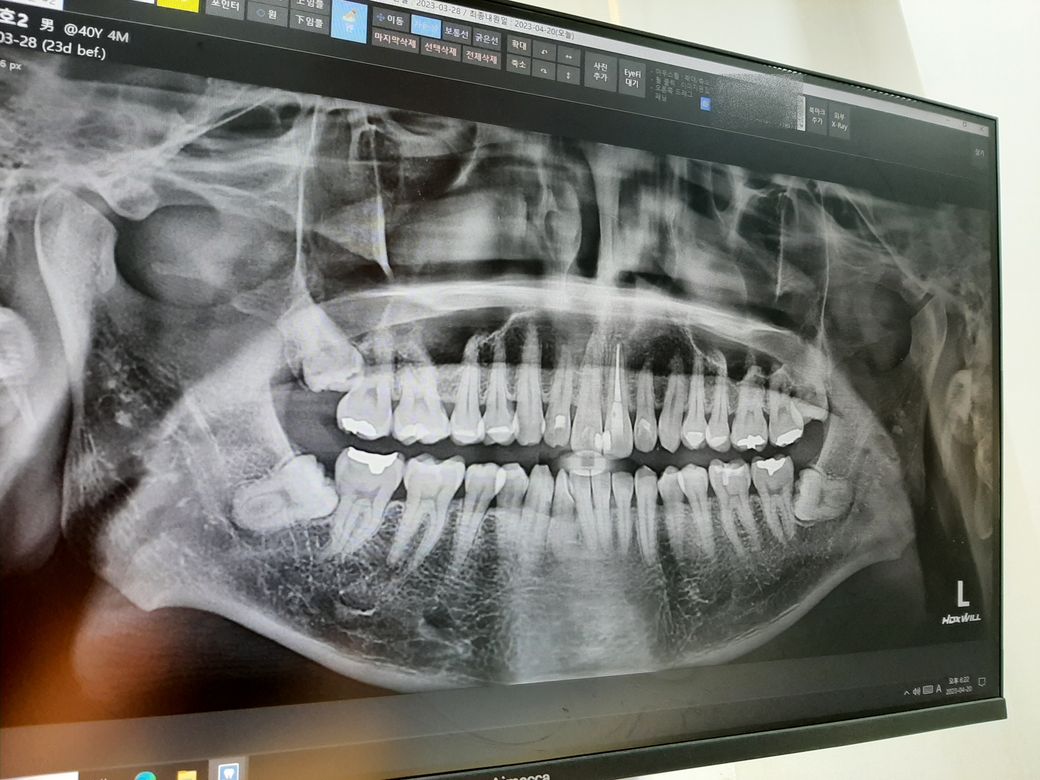

전체 사진

작년에 사랑니 3개를 뽑고 현재 남은 왼쪽 사랑니를 뽑으려고 예약하고 구강악안면외과 치과 방문하니

1. CT 찍어보니 사랑니에 신경이 지나가서 발치 시 건드릴 수 있다. 그러면 안면마비가 오고 회복이 안 될 수 있다.

2. 왼쪽 사랑니는 잇몸으로 덮여 있고 사진 상으로는 어금니와 사랑니 사이에 충치나 염증이 있어 보이진 않는다.

3. 환자가 지금 사랑니 쪽 통증이라기보단 예방 목적으로 뽑으려는 거라 발치를 권유하진 않는다.